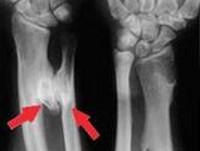

Диагноз выставляется на основании совокупности клинических и рентгенологических признаков. При этом решающую роль в постановке окончательного диагноза обычно играет рентгенография. Иногда в качестве дополнительных методов исследования также используется магнитно-резонансная томография и компьютерная томография.

На рентгенограммах выявляется изменение контуров кости, обусловленное наличием опухолевидного образования, связанного с основной костью широкой и толстой ножкой. Поверхностные отделы образования имеют неровные контуры и по своей форме могут напоминать цветную капусту. В отдельных случаях ножка отсутствует, и остеохондрома прилегает к «материнской» кости. Контуры остеохондромы четкие, непрерывные, непосредственно переходящие в контуры основной кости.

Хрящевая шапочка на рентгеновских снимках обычно не определяется за исключением случаев, когда в ней есть очаги кальцификации. Поэтому не следует забывать, что реальный диаметр остеохондромы может на 1-2 см превышать диаметр, определяемый по данным рентгенографии. При подозрении на увеличение размеров хрящевой шапочки необходимо проведение магнитно-резонансной томографии.